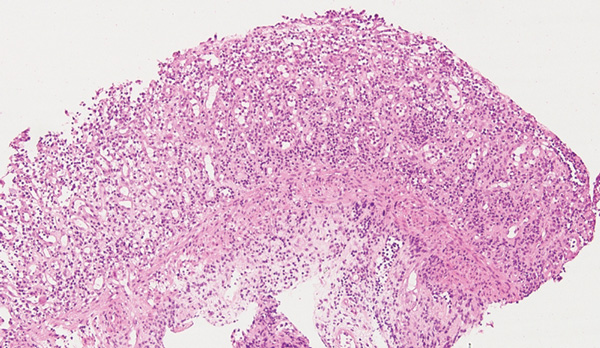

A 32-year-old Indigenous man from a remote Western Australian community presented with a fever, diffuse papular rash and oral ulceration, and a productive cough of 2 weeks’ duration. He was admitted to the intensive care unit (ICU) for respiratory failure and hypotension. Phenytoin 300 mg daily had been prescribed 3 weeks earlier for alcohol-associated seizures. He remained febrile with persistent respiratory failure, and after 10 days he developed profuse diarrhoea and transient hepatitis. Abdominal imaging results were normal and screening tests for bloodborne infections and autoimmune disease were negative. Colonoscopy showed severely inflamed, oedematous mucosa and confluent ulceration, with histological evidence of widespread mucosal loss and granulation tissue overlying inflamed superficial submucosa with prominent cytomegalovirus (CMV) inclusions (Box 1 and Box 2).